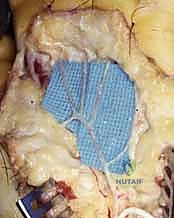

Flatt Digital Sympathectomy Technique

The Flatt Digital Sympathectomy is the cornerstone procedure for medically refractory Raynaud's phenomenon with patent inflow. The objective is the precise mechanical ablation of the sympathetic nerve fibers traveling within the arterial adventitia. Under high magnification, the common digital arteries and their proper digital branches are identified as they emerge from beneath the superficial palmar arch.

The first critical step is the isolation of the digital artery from the adjacent proper digital nerve. These structures are intimately bound by delicate fascial bands. Using fine micro-forceps and micro-scissors, the surgeon meticulously separates the artery from the nerve over a distance of 1.0 to 2.0 cm. Extreme vigilance is maintained to avoid any traction or direct trauma to the nerve, which could precipitate a painful postoperative neuroma.

Once the artery is isolated, the adventitial stripping commences. The surgeon stabilizes the arterial wall with one set of non-toothed jeweler's forceps. With a second set of forceps, the thin, translucent outer adventitial layer is grasped. Using a highly controlled, peeling motion—akin to removing the thin skin from a grape—the adventitia is stripped circumferentially from the underlying muscularis media.

As the adventitia is removed, the visual appearance of the artery changes dramatically; it transitions from a slightly opaque, tethered vessel to a smooth, highly translucent, and often visibly dilated conduit. This visual cue is the hallmark of a successful sympathectomy.

Concurrently, the surgeon must identify and sharply divide any microscopic tethering branches or fine neural connections bridging the proper digital nerve and the arterial wall, as these frequently carry aberrant sympathetic fibers.

Radical Digital Sympathectomy and Microvascular Considerations

In patients presenting with profound, widespread vasospasm or severe ischemic ulcerations involving multiple digits, a localized Flatt sympathectomy may be insufficient. In these severe cohorts, a radical or extensive digital sympathectomy is indicated. This highly aggressive approach involves skeletonizing the arterial tree from the distal forearm down to the proper digital arteries.

The dissection begins proximally, stripping the adventitia from the distal radial and ulnar arteries as they enter the wrist. The superficial palmar arch is entirely exposed and denuded of its adventitial layer.

This extensive dissection requires navigating the complex neural anatomy of the palm, particularly the branches of the median and ulnar nerves, ensuring they are gently retracted and protected.

If, during the exploration, an area of fixed occlusion or a thrombosed aneurysm (such as in hypothenar hammer syndrome) is encountered, the procedure transitions from sympathectomy to microvascular reconstruction. The diseased arterial segment is resected until healthy, pulsatile intima is visualized proximally and distally. An autologous reversed saphenous vein graft is harvested, prepared, and interposed into the defect. End-to-end microvascular anastomoses are performed using 8-0 or 9-0 non-absorbable monofilament sutures under the microscope, ensuring precise intimal coaptation to prevent turbulent flow and re-thrombosis.

Upon completion of either sympathectomy or bypass, the tourniquet is deflated. The surgeon observes the extremity for the return of brisk capillary refill and the resolution of pallor. Topical vasodilators, such as papaverine or lidocaine, may be applied directly to the vessels to counteract any mechanically induced vasospasm. Meticulous hemostasis is achieved using bipolar electrocautery before the skin flaps are loosely approximated to accommodate postoperative edema.